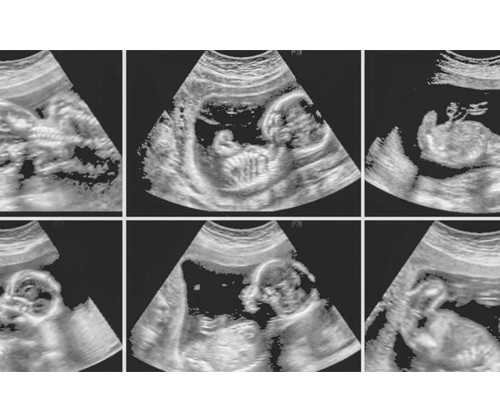

上海试管婴儿费用大约在1万左右试管婴儿就是采用人工方法让卵细胞和精子在体外受精,并进行早期胚胎发育,然后移植到母体子宫内发育而诞生的婴儿。